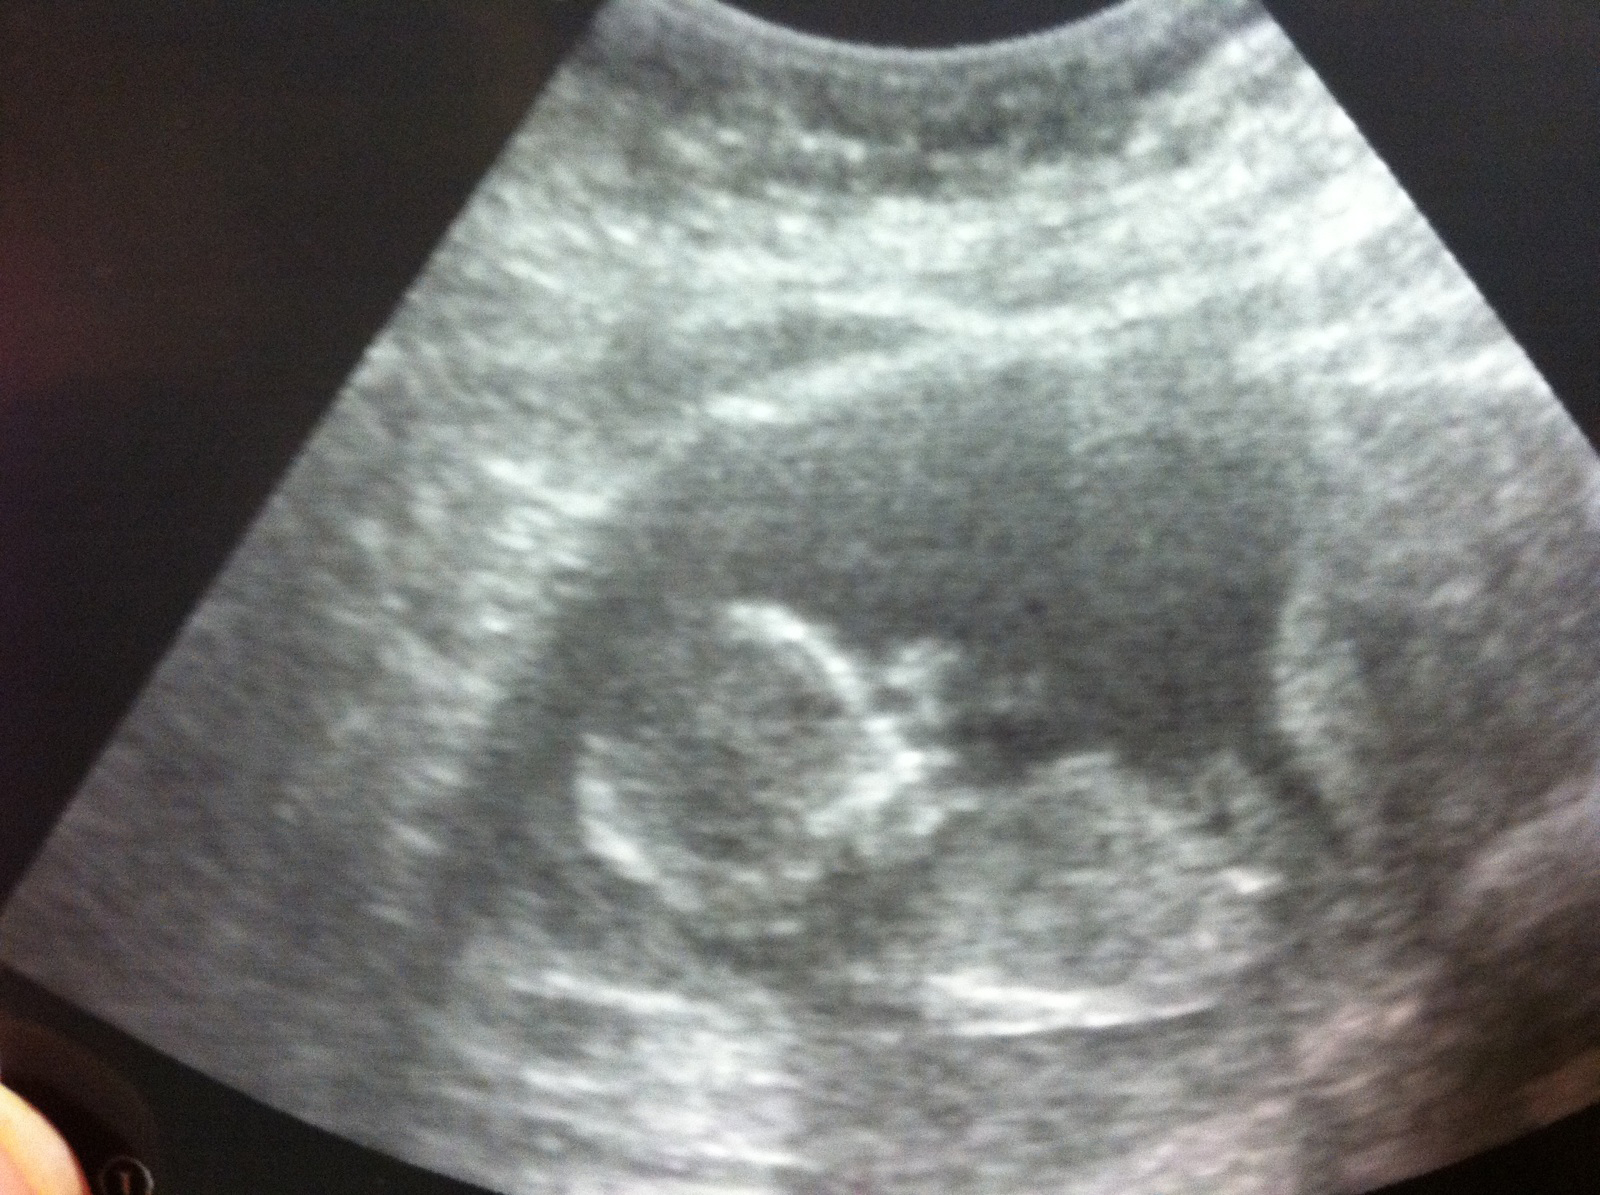

Super Good: Today I had another ultrasound, basically a "You were really sick, let's check on the baby" ultrasound, and he looked great. Measuring ahead at 13 weeks 3 days, with a heart rate of 162. I was so relieved. Here's a pic of the little man. He is either waving hello, or it appears that there is a weird alien face in there with him (I prefer the "waving" idea).